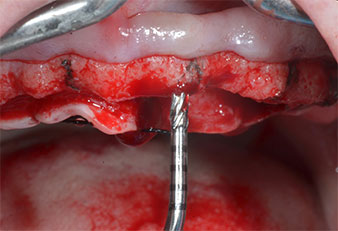

A flame-shaped, diamond-coated piezoelectric instrument (Piezomed I1) was used to mark the implant positions and to perform pilot preparation (Fig. 3). Care was taken to use an up and down movement, with reduced power, full irrigation and low pressure (below 300 g). Next a pilot instrument (Piezomed I2A/I2P) was applied for the initial 2 mm diameter enlargement of the implant sites (Fig. 4), followed by a 3 mm insert (Fig. 5).